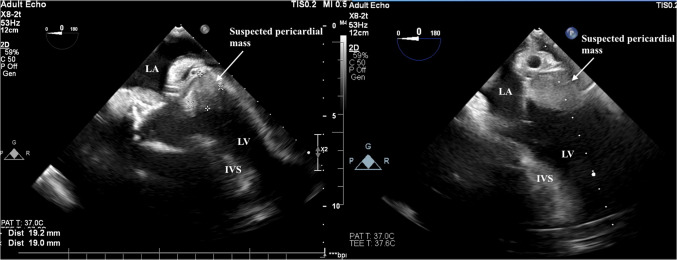

In this short report, we present a rare scenario involving a 60-year-old male patient, in whom higher pump speed and suction mimicked external compression of the left ventricle. Surgical revision revealed excessive suctioning of the left ventricle and left atrium by the left ventricular assist device, leading to atrioventricular groove distortion that mimicked external compression of the left ventricle. After adjustment of the pump speed, obstruction of the inflow cannula and collapse of the left ventricle were resolved.